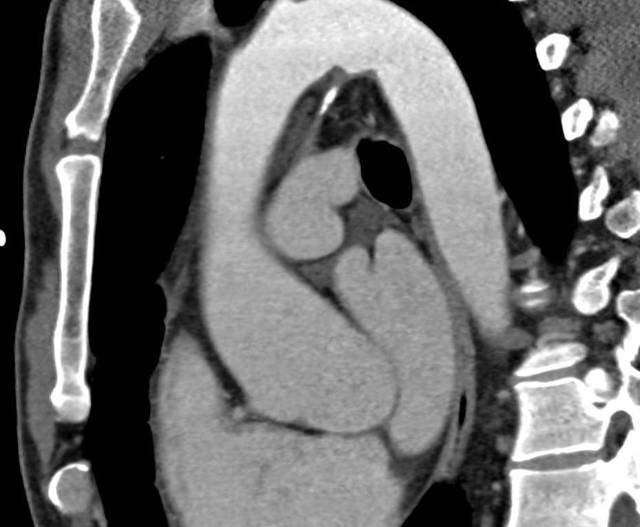

- Рентген грудной клетки в прямой и боковой проекциях. На снимках хорошо видны крупные сосуды, по виду которых врач делает вывод о наличии патологии. При утолщении аорты меняется ее изгиб, удлиняется тень. По этим признакам специалист определяет величину закупоривания.

- Информативным является рентгенографическое исследование, флюорография. Аорта уплотнена (что это значит и почему развивается, вы уже знаете), ее тень на снимке удлинена, возможно появление патологического разворота или нехарактерного изгиба по ходу сосуда.

- Рентгенографический снимок грудной полости в прямой и боковой проекциях. Врач-рентгенолог сможет разглядеть на снимке характерные изменения, подтверждающие патологию. Если подозревается изменение в брюшной части аорты, то делают снимок брюшной полости.